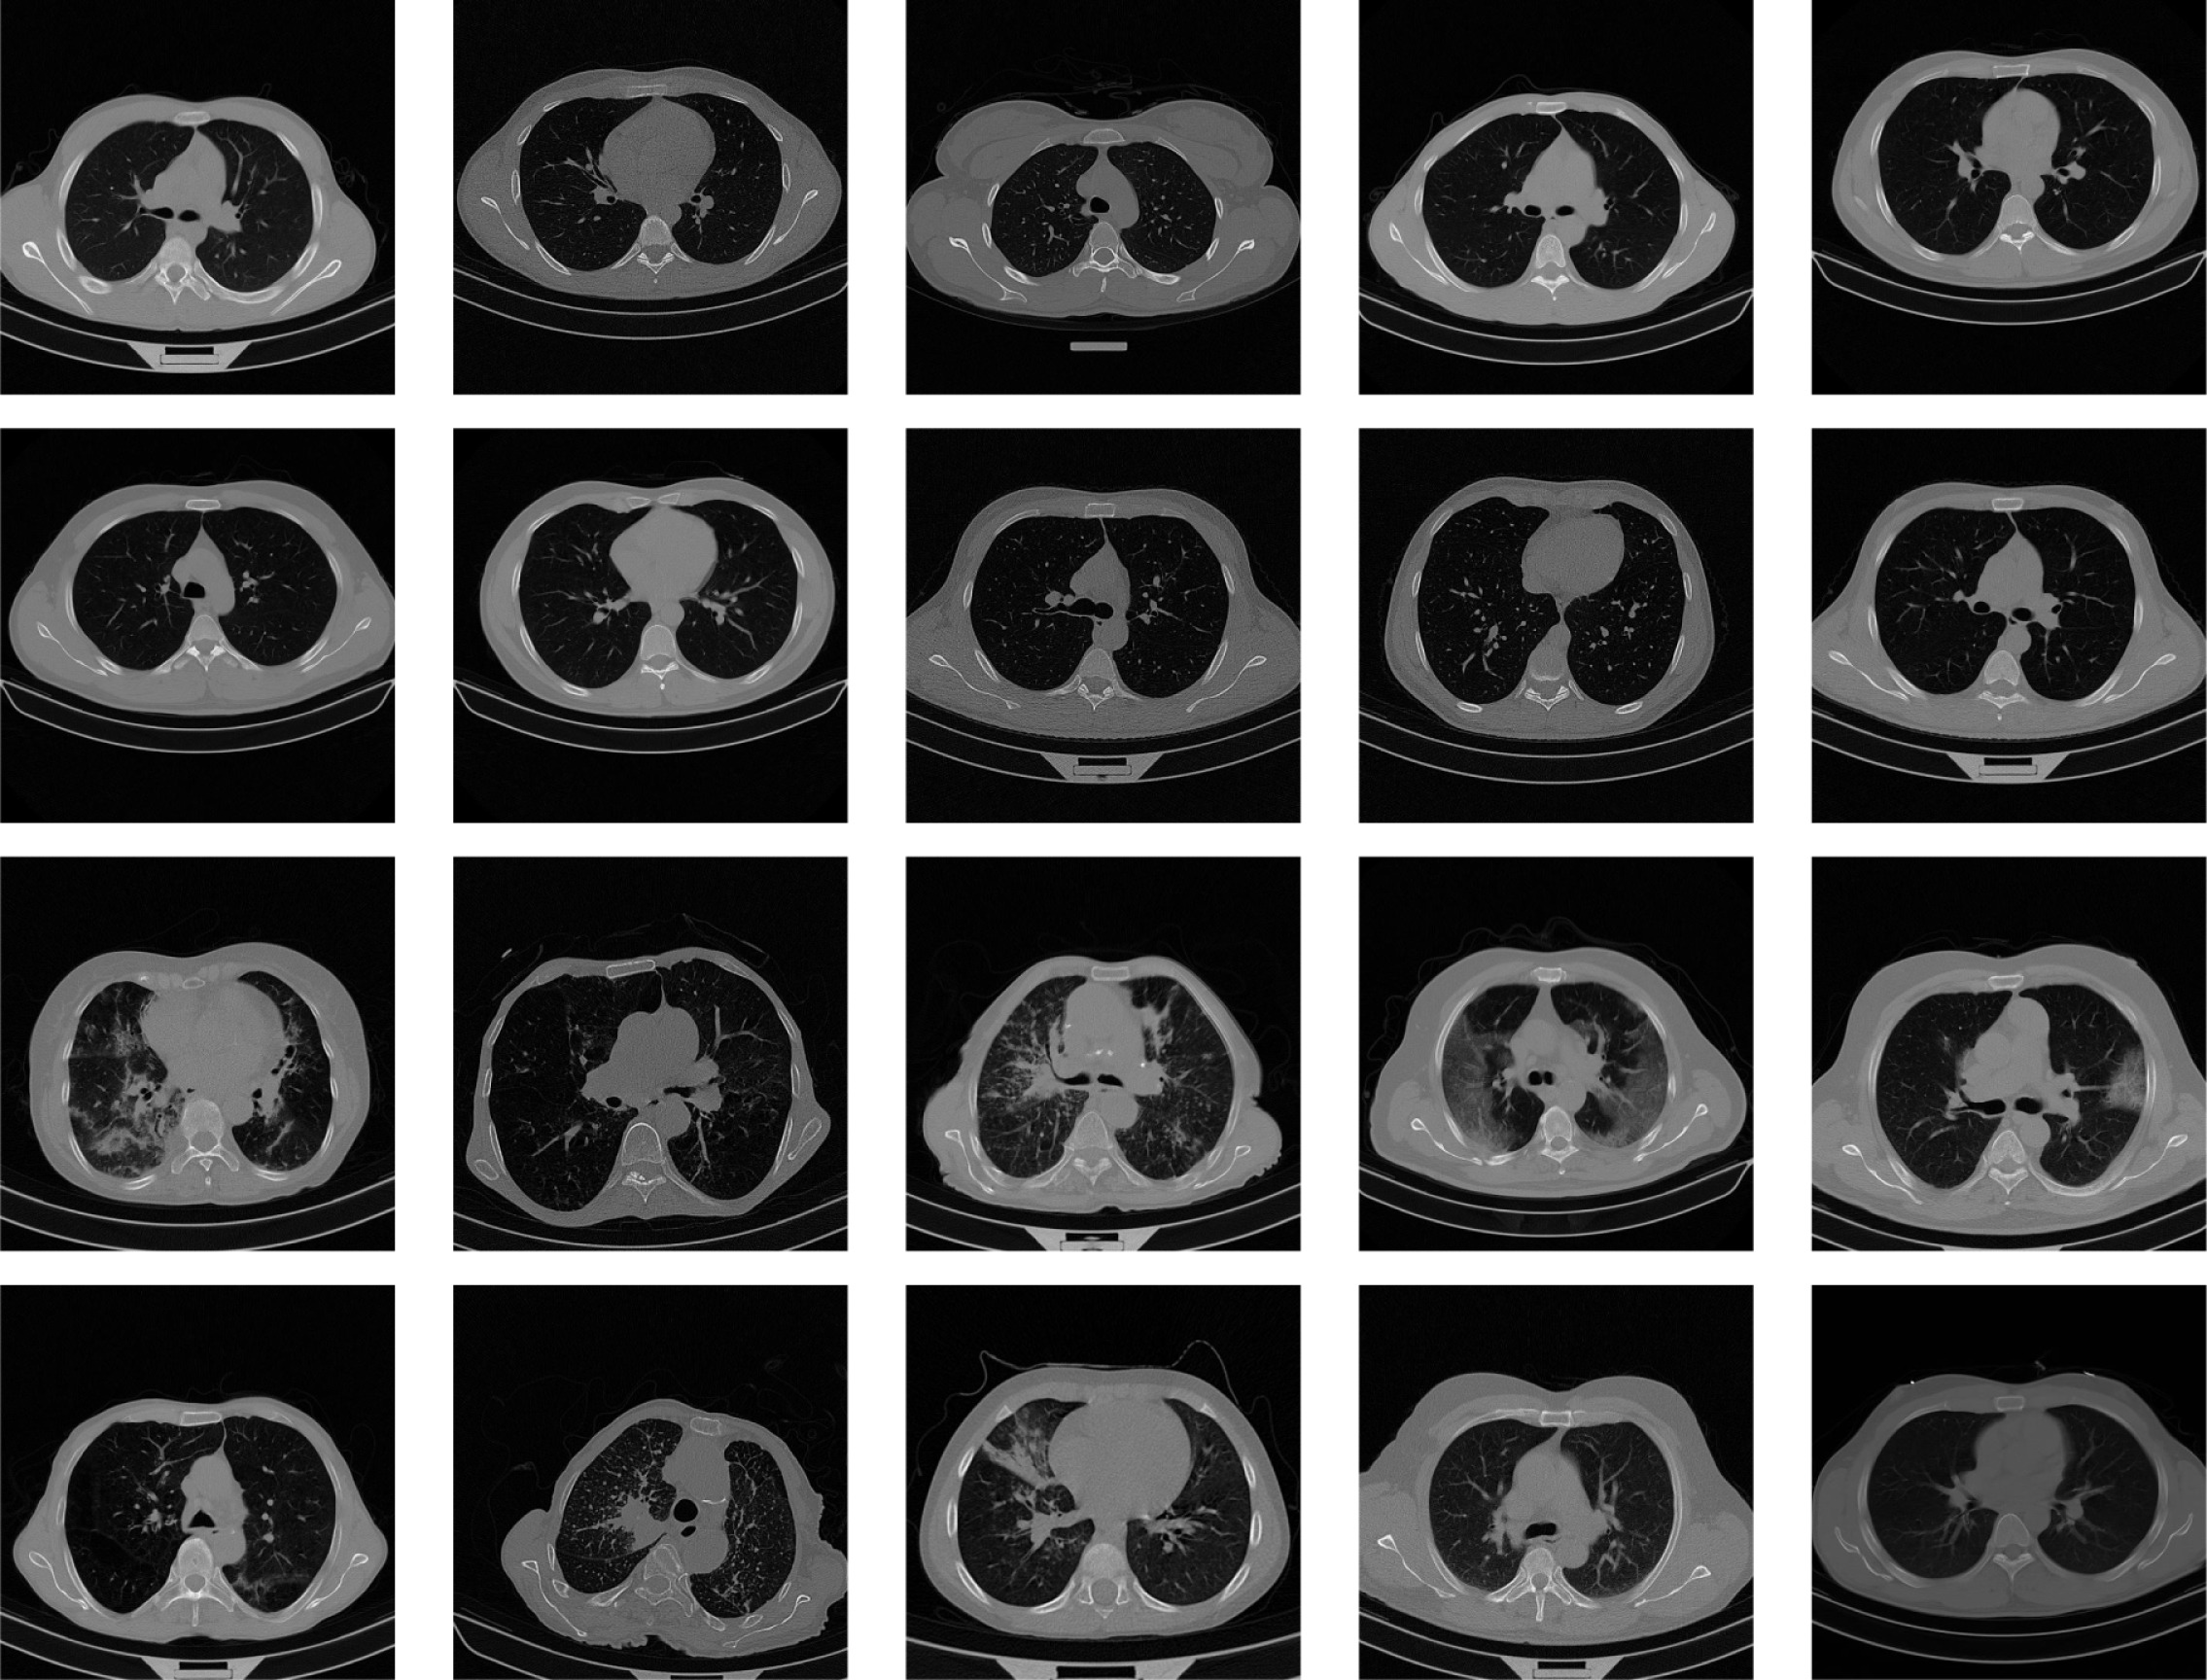

The rapid global spread of Coronavirus Disease 2019 (COVID-19) highlighted the critical need for rapid and accurate diagnostic tools to manage the pandemic and mitigate its spread. While Reverse Transcription Polymerase Chain Reaction (RT-PCR) tests were the gold standard for confirmation, their shortage during peak outbreaks necessitated alternative diagnostic methods.[1] Computed Tomography (CT) scans emerged as a valuable tool for screening and diagnosing COVID-19, as they have been shown to be more sensitive than RT-PCR tests.[2] The analysis of CT scans is a time-intensive process that requires specialized medical expertise, which can be a significant bottleneck, especially for overwhelmed healthcare systems or in underdeveloped areas. As illustrated in Figure 1, the CT scans of COVID-19 and non-COVID patients exhibit no readily apparent differences discernible without expert evaluation.

Refer to caption

Figure 1: Examples of CT scans, first two rows contain images from healthy subjects, whereas the last two rows contain images from COVID-19 patients.[4]